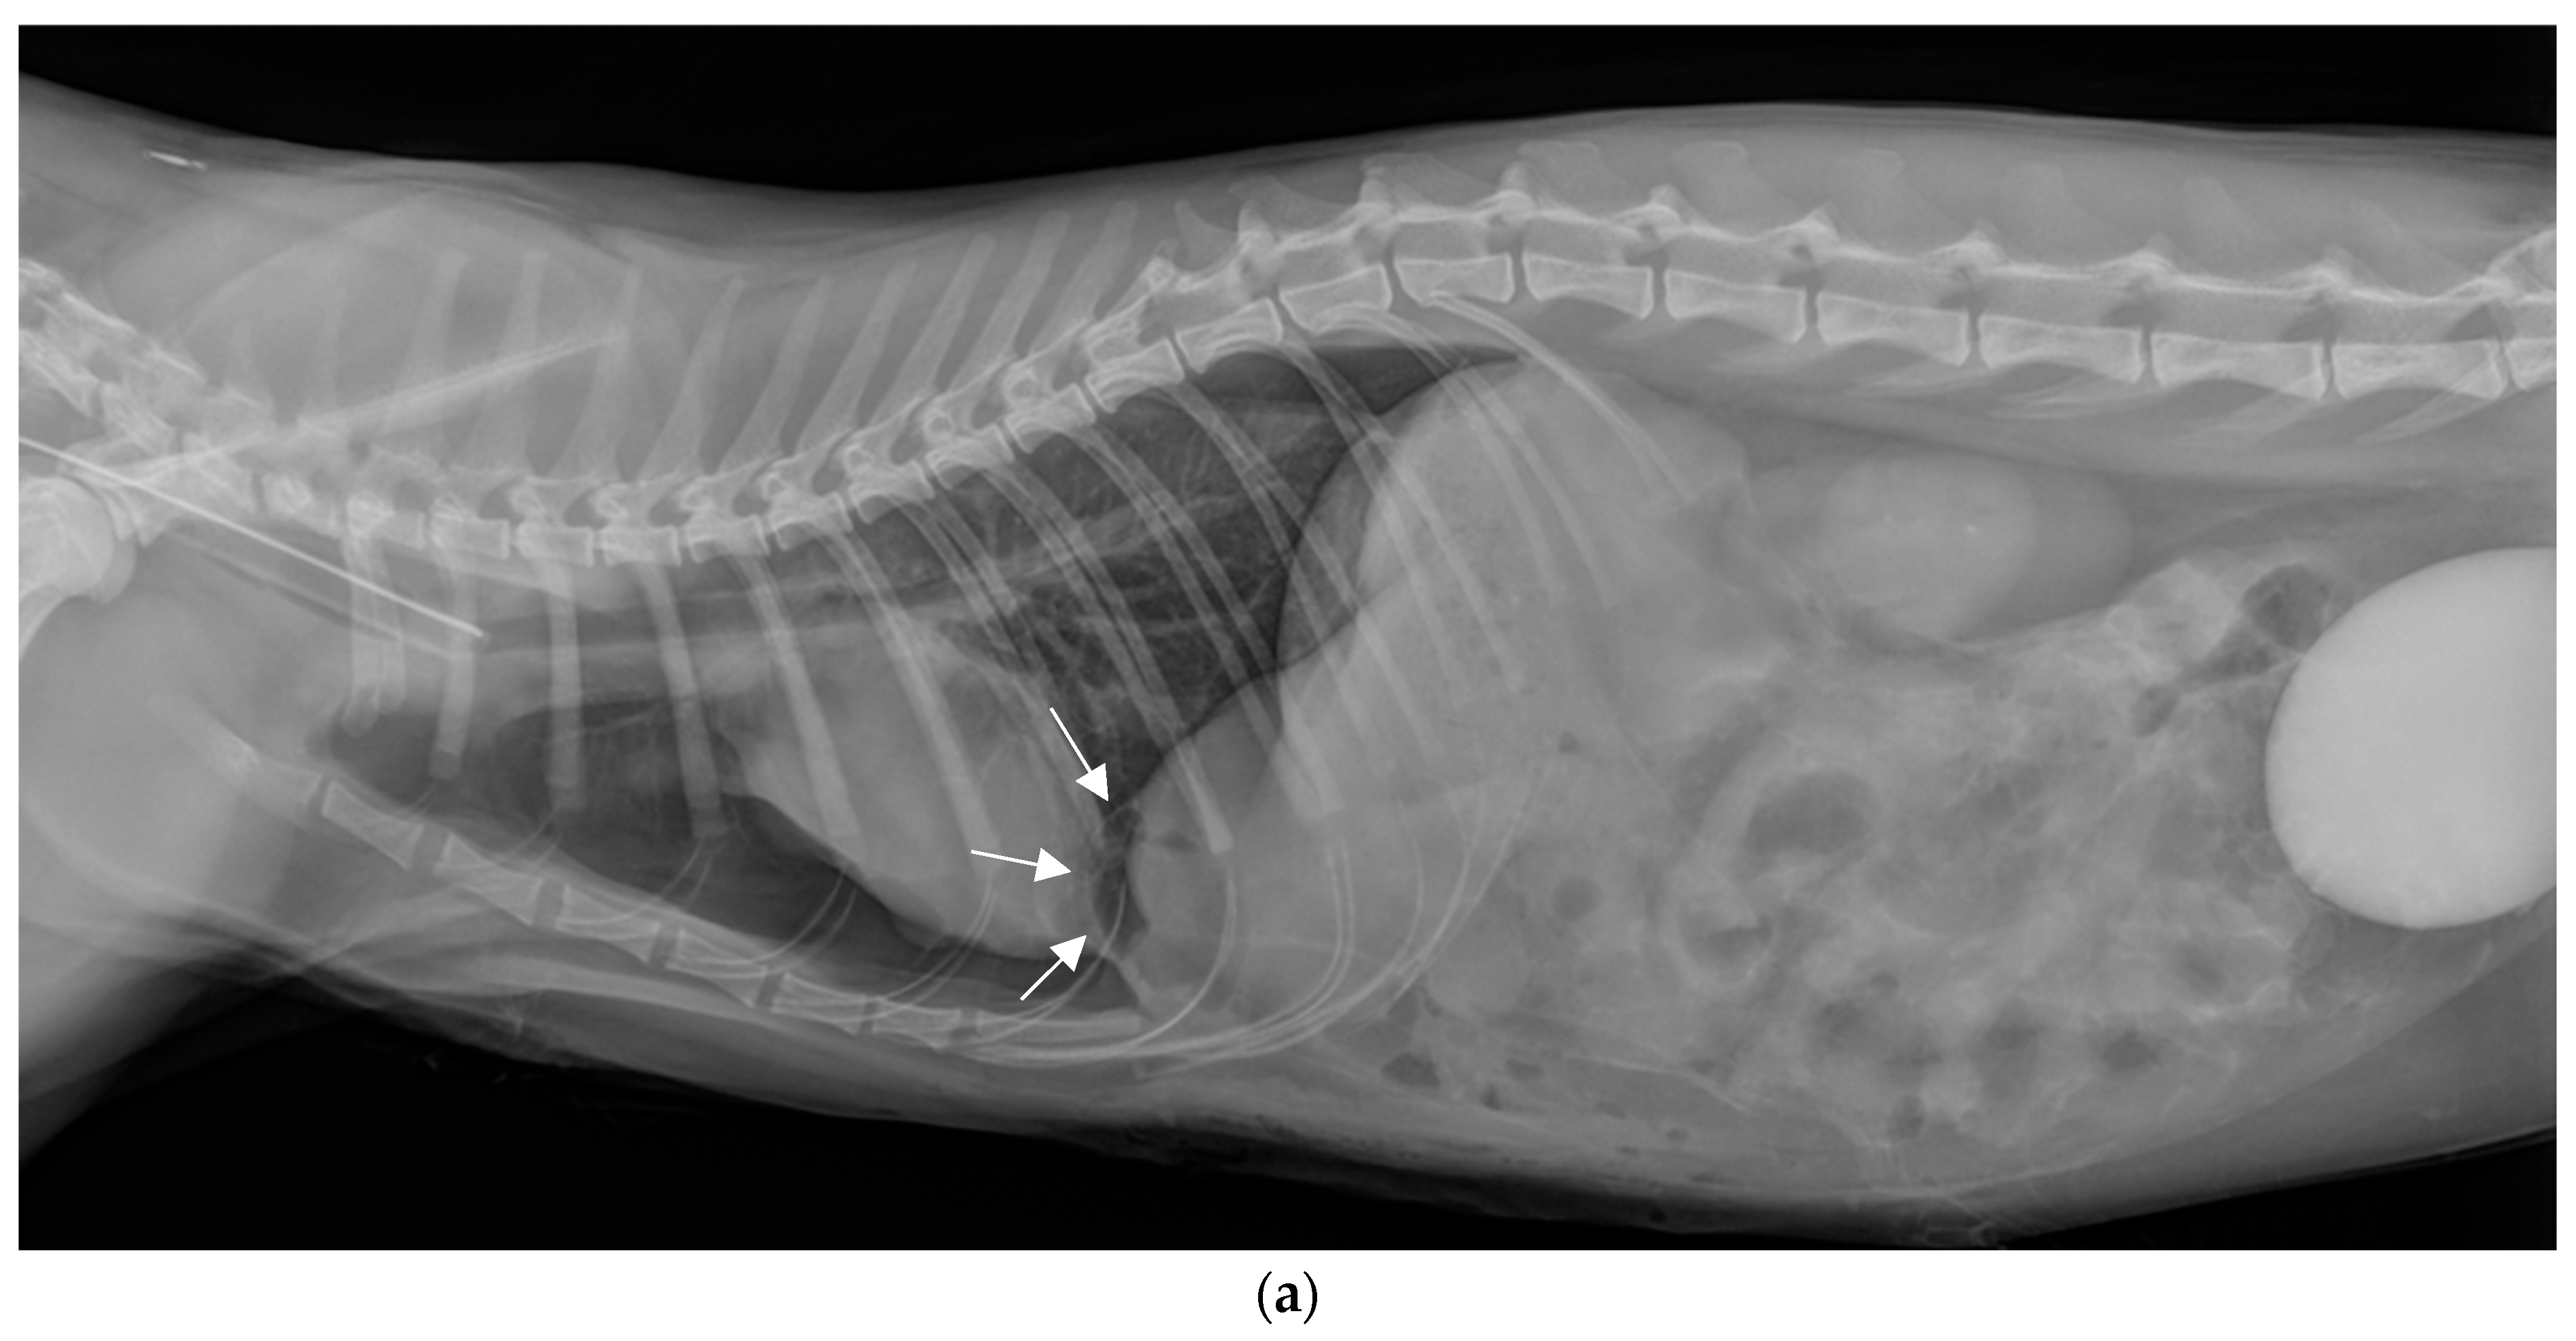

2.4. Surgical Treatment

2.5. Postoperative Phase